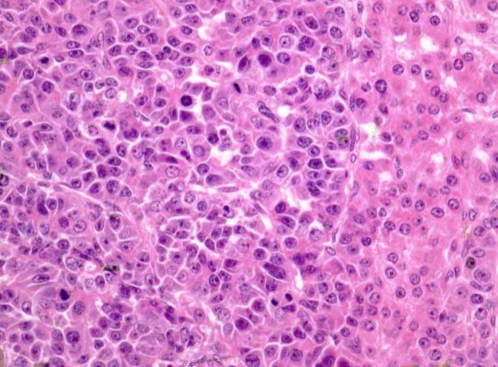

Immunohistochemical examination revealed a corresponding positive reaction with cytokeratin, EMA (epithelial membrane antigen), vimentin, polyclonal CEA (carcinoembryonic antigen), Hep Par-1, AFP (alpha-fetoprotein), alpha 1-antitrypsin, CD 99, CD 56, hCG (human chorionic beta-gonadotropic hormone), transferrin receptor and delta-like protein [7]. | Figure 2. Hepatoblastoma is a site with an embryonic component. Increase .x200. H&E |

Microscopy revealed extensive areas of hemorrhage in the tumor tissue. Marked lymphoid infiltration of the portal tracts was noted. The pathohistological diagnosis is epithelial type hepatoblastoma (fetal and embryonic components). This epithelial-type hepatoblastoma demonstrates a fetal "mature" pattern (the right part of the drug), passing into the embryonic "immature" zone (the left part), which clearly emphasizes the contrast between the two subtypes. Fetal areas resemble mature hepatic parenchyma and are characterized by relative cellular homogeneity, minimal atypia, rare mitoses, and tumor cells with abundant eosinophilic cytoplasm. The embryonic areas look less mature, with a high nuclear-cytoplasmic ratio, more pronounced cellular atypia and increased mitotic activity (Fig. 3).  | Figure 3. Epithelial type hepatoblastoma. Fetal "mature" pattern (right side), embryonic "immature" area (left side). Increase .x200. H&E |